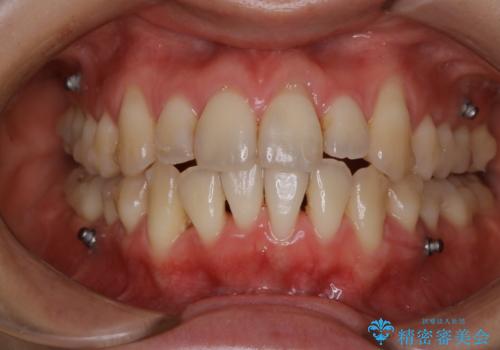

- 初めてのホワイトニングで一日で歯を白くしたいということでご来院されました。

黄ばみがとれ、歯の色が1トーン上がりました。歯肉退縮があったため、その部分は保護をして薬剤が触れないよう配慮しながら施術を行いました。